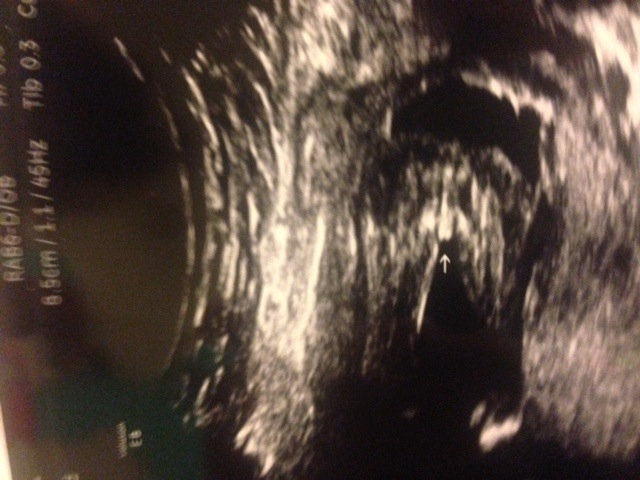

I'm having my first baby. We went in for the "big reveal" at 18+5. It was a 3D ultrasound. The baby looked great, all its little baby parts in order and they told us it was a girl!

We were very excited, but a bit confused. We both thought we were actually looking at a picture of a boy. I've been studying the three-white lines of confirmed girl ultrasounds, but this looks a bit different. The line in the middle (with the arrow) seems to be, eh, protruding! It also looks like it might be two lines? Or am I looking at the wrong thing? Are the two thick white lines on the side her legs or her labia? Or neither because she's actually a he!

Is it the center bit that I should be focusing on?

Attachment 14590